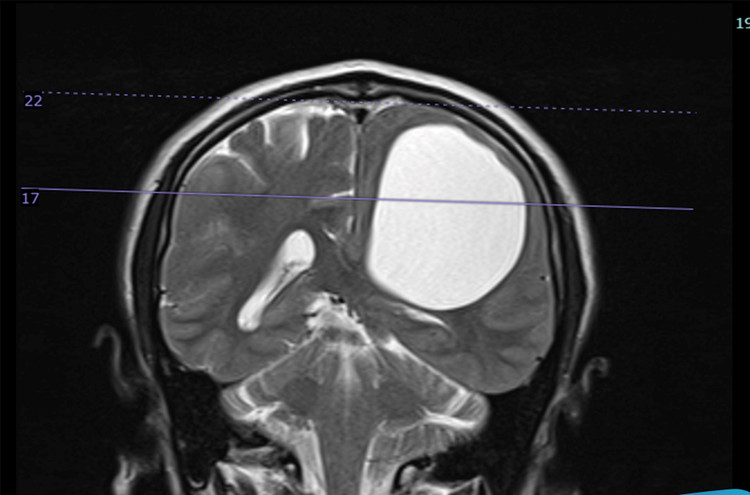

Sau khi tiến hành thăm khám, chụp chiếu, kết hợp với các biểu hiện lâm sàng, người bệnh được hội chẩn và chẩn đoán đa u nang trong não, chưa loại trừ nang sán não. Trong nhu mô não có rất nhiều nang to, nhỏ. Trong đó, nang kén lớn nhất kích thước khoảng 5cm x 7cm, đè ép nhu mô não khiến người bệnh yếu, liệt nửa người.

| Ảnh MRI trước mổ của bệnh nhân liệt nửa người: Nang sán lớn nhất nằm trong nhu mô bán cầu não bên trái |